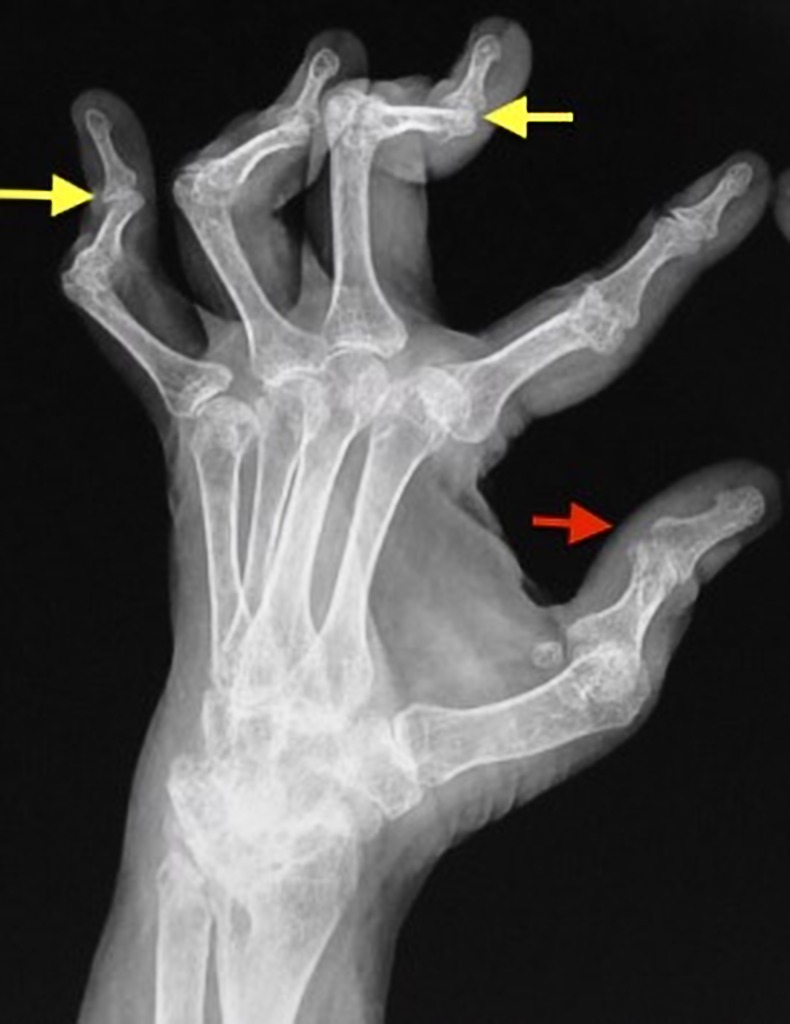

Boutonniere deformity - contracture associated with RA

swan neck deformity-associated with RA

hitch-hiker thumb - associated with RA